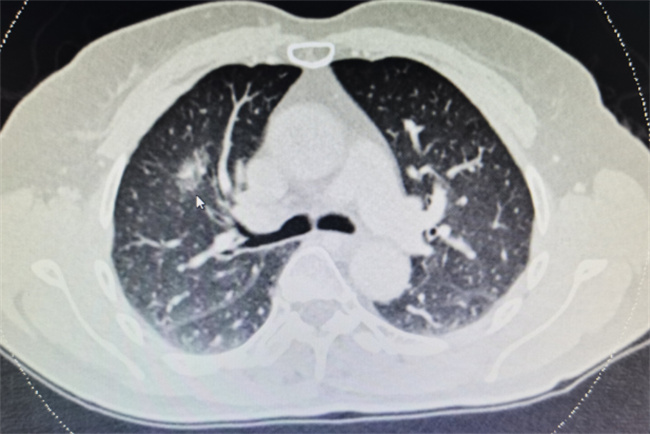

有些良性确诊患者在平台上马上就会晒出自己的CT报告,并且还会显示肺部会有明显的白肺情况,建议大家在新冠感染康复之后,就应该马上去做肺部CT检查。许多的人在转阴之后还有咳嗽,而且咳嗽持续了较长的一段时间,因此都会选择来到医院做肺部CT检查,最近一段时间做肺部CT检查的人非常的多,甚至已经达到一个人满为患的现象,但是其中出现严重肺部疾病的人并不是很多,估计仅仅只有1%~2%左右。

如今所出现的这些肺部影像并非是医学上所说的白肺。临床上主要是指一种肺源性的肺水肿,而且在显示上面就会看到有白色的斑影片,一般这就是因为病毒感染所导致,一般情况是比较轻微的,并不需要过于的担心,再过了一段时间之后就会逐渐的恢复。除了新冠病毒之外结合杆菌感染又或者是流感病毒都有可能会导致肺炎的出现,一般的情况下都是可以恢复的,哪怕是一些比较严重的患者在干预之下也会慢慢的好转,因此也并不需要特别的惊慌。实在担心的话,就可以直接选择去拍一个胸片,就可以显示出很多的问题,然后就可以采取针对性的治疗。